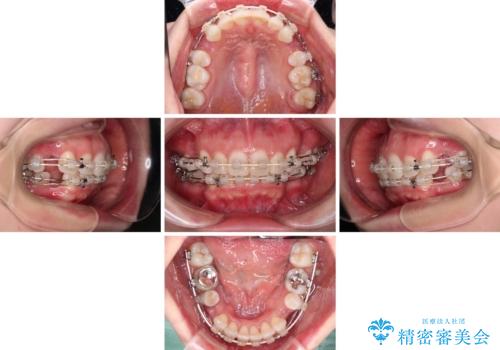

- 口元の閉じにくさと、奥歯の咬み合わせを気にして来院された患者様です。

左下の大臼歯2本が顕著に舌側に傾斜しているため、まずは奥歯の咬み合わせを改善をし、その後上下左右の第1小臼歯4本を抜歯することで口元を引っ込めながら整えることとしました。

奥歯の咬み合わせ改善には1年ほどの期間と処置中の噛みにくさを強いることとなりましたが、抜歯後はスムーズに治療を完了させることができました。

歯ぎしりの際に奥歯が干渉していた咬み合わせも理想的な状態に改善できました。